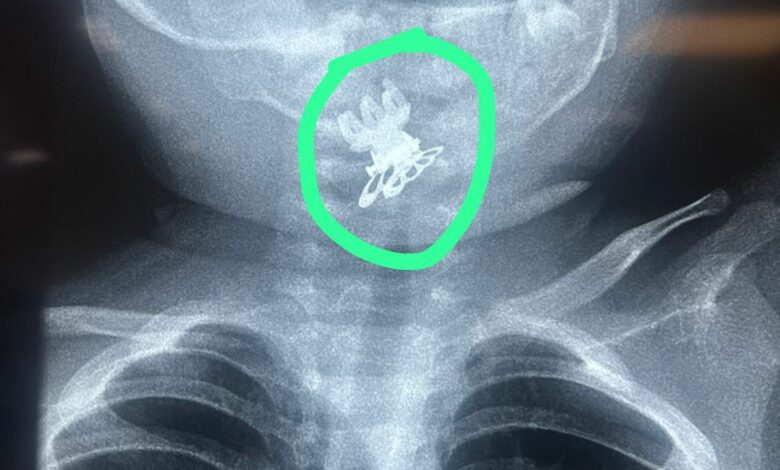

تمكّن فريق طبي في مدينة الصدر الطبية من إنقاذ حياة طفلة بعمر سنة ونصف بعد تعرضها لحالة اختناق شديدة نتيجة ابتلاعها مشبك شعر (قرّاصة) استقر في مدخل المجرى التنفسي.

وأوضحت الطبيبة الاختصاص جراحة الأنف والأذن والحنجرة الدكتورة فرقان حميد محمد” أن الطفلة أُدخلت إلى صالة عمليات الطوارئ وهي تعاني من اختناق وسعال شديدين وعلى الفور تم إجراء الفحوصات والأشعة اللازمة التي أظهرت وجود جسم غريب في مدخل المجرى التنفسي.استخراج مشبك شعر (قرّاصه)من مجرى التنفس لطفلة بعمر سنة ونصف في مدينة الصدر الطبية

وأضافت أن الفريق الجراحي برئاستها وبمشاركة الأطباء المقيمين الأقدمين إلى جانب فريق التخدير والتمريض باشر بإجراء عملية دقيقة باستخدام الناظور حيث تم استخراج مشبك الشعر بنجاح دون مضاعفات.

وأكدت أن الطفلة خرجت من العملية وهي بصحة جيدة بعد استقرار حالتها مشيدةً بجهود الفريق الطبي والجراحي والتنسيق العالي الذي أسهم في إنقاذ حياة المريضة